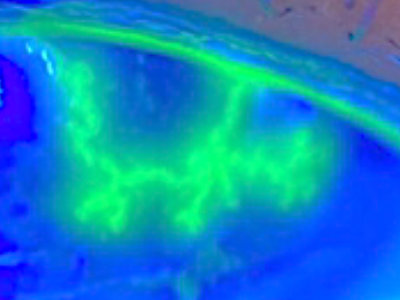

左:緑の染色液と青色光を用いて観察した角膜炎の病変。右:数理モデルによって再現された病変の形。

実際の病変

数理モデル